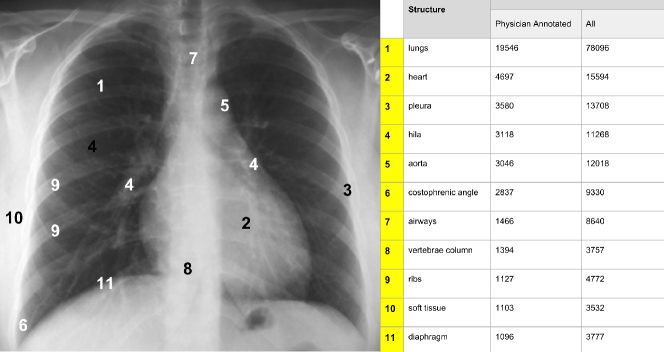

Anatomic locations were annotated with 104 different labels. In the 249,469 locations specified, the majority of the findings and/or diagnoses were localized in the lung fields (78,888 findings, the majority being - 34,661 - in the lower lung fields), followed by mediastinum (39,134 findings, the majority being in the lower mediastinum in the cardiac region), bone (12,862 findings) and soft tissue (3,567 findings). There were 13,935 findings reported in the pleural region, 11,349 in the hilar region, 9850 aortic findings and 3,777 diaphragmatic findings, as shown in Fig. 15.